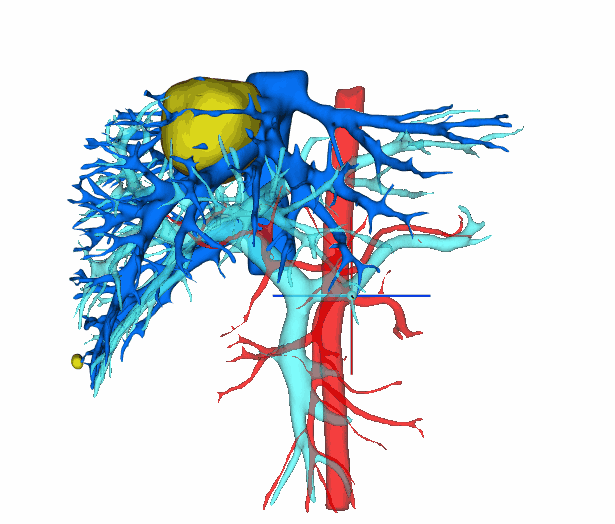

面对患者及家属的深切忧虑,以韩彦华主任医师及王玮副主任医师为核心的肝胆外科团队迎难而上。术前,团队借助先进的3D可视化成像技术,对肿瘤位置、大小及其与周边血管的立体关系进行了精确“测绘”,制定了周密的手术预案。术中,主刀医生王玮凭借精湛的显微外科技术和术中超声实时导航,在错综复杂的“血管丛林”中精准辨识、精细游离,如同进行一场精密的“生命拆弹”。麻醉团队全程护航,严密监控生命体征,为手术安全提供了坚实保障。

基于CT影像的3D重建技术